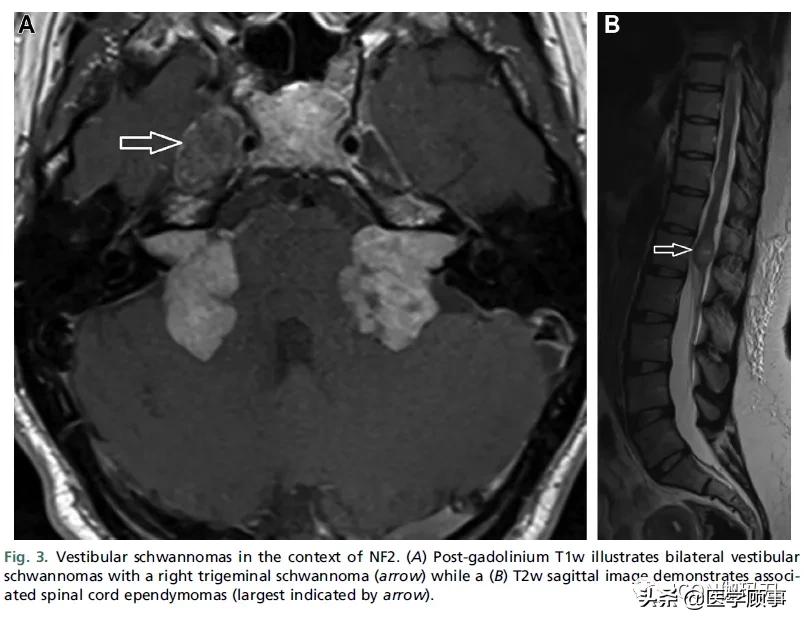

5%的患者存在双侧前庭神经鞘瘤(VSs),是神经纤维瘤病2型(NF2)的标志。NF2是一种常染色体显性肿瘤易感性疾病,出生发病率为1 / 25至33000。嵌合体(mosaic)型NF2患者可能表现为单侧前庭神经鞘瘤(VSs),但通常会有临床特征或家族病史。NF2前庭神经鞘瘤(VSs)的特点是年龄较轻,生长较快,并在耳蜗内延伸。NF2还与其他颅神经神经鞘瘤和脑膜瘤有关,可能在后颅窝发生碰撞瘤。全神经轴成像是合适的,因为75%的患者也会发生脊柱内的神经鞘瘤和室管膜瘤(图3)。

图3。NF2背景下的前庭神经鞘瘤。(A)钆剂后T1w显示双侧前庭神经鞘瘤伴右侧三叉神经鞘瘤(箭头),而(B) T2w矢状(#`O′)图显示相关的脊髓室管膜瘤(箭头指示最大的肿瘤)。